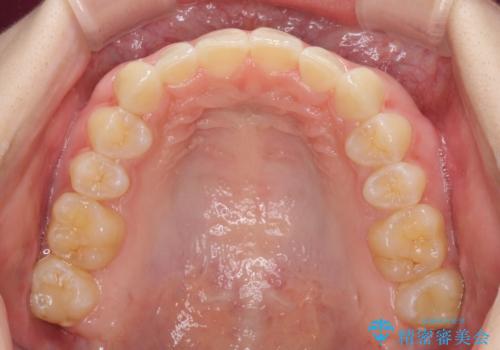

前歯のデコボコを治したい インビザライン矯正治療

- 前歯のデコボコ気になるとのことで来院された患者様です。

下顎骨が上顎骨に対して右側にシフトしており、さらに下顎が後方に位置しているため、非常に強い咬合力で食いしばっている状態でした。

上下顎ともに歯列全体の後方移動とIPR(歯と歯の間を削る)によってデコボコが解消するように設計し、インビザラインにより治療を行うこととしました。

強い咬合力による臼歯部の噛みにくさと、それに伴う歯の移動の鈍さに悩まされ、非常に長い期間を要することとなりました。

上下正中位置は、治療開始時よりは改善したものの、ここが限界であろうというところでのゴールとなりました。

下顎前歯の大半が隠れている状態ですが、左右への歯ぎしりはスムーズに行うことができ、就寝時には後戻り防止も兼ねて、食いしばり対策としてマウスピースの使用を継続するようお願いしております。